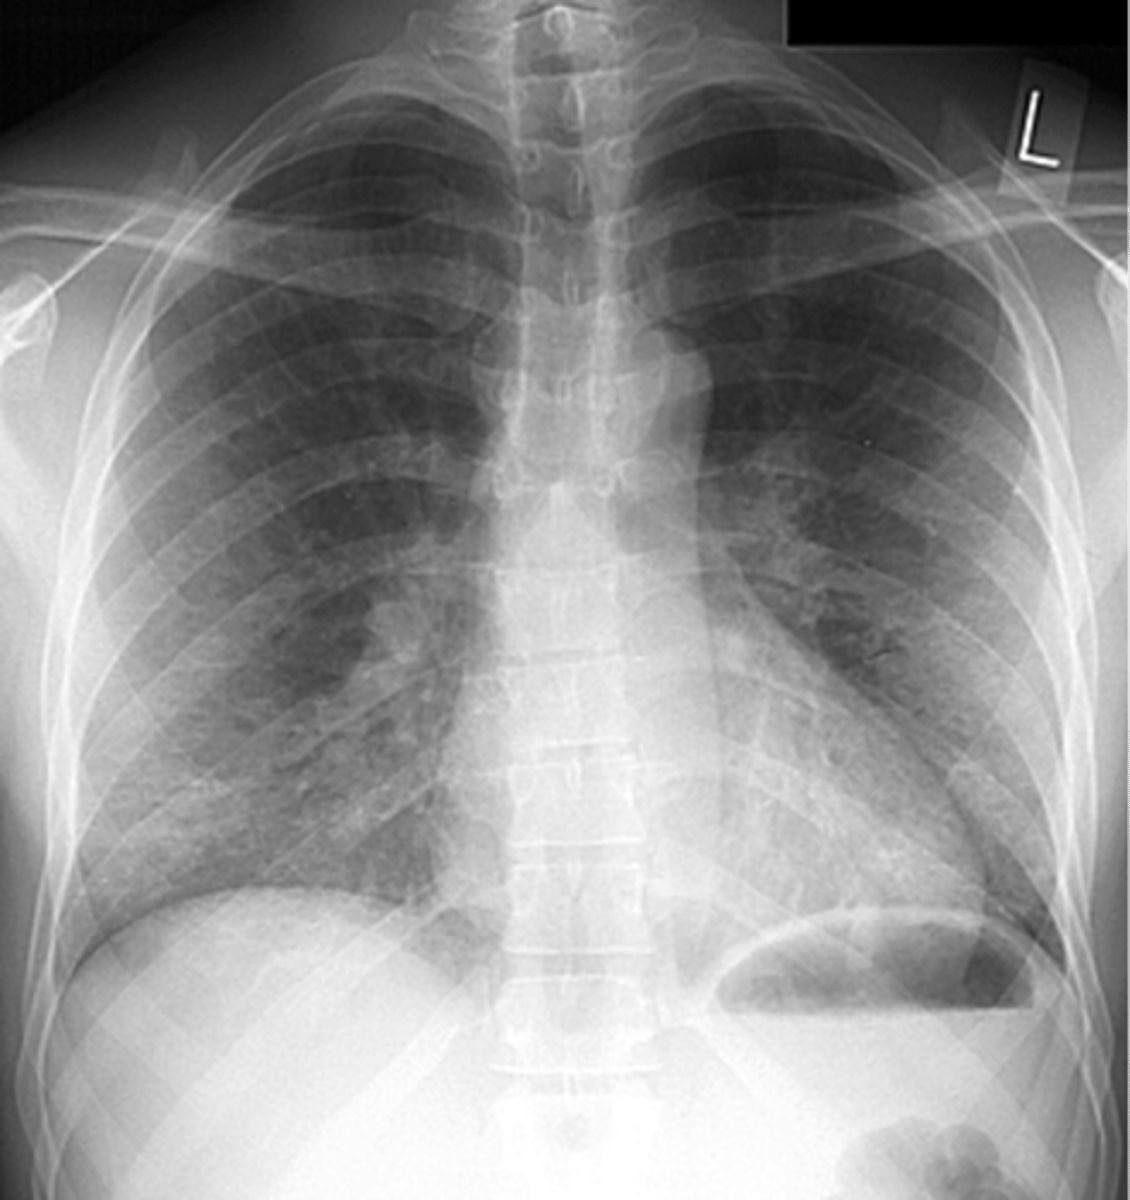

community acquired pneumonia

Silhouette sign

spine sign

Silhouette sign right cardiac border- RML infiltrate

Silhouette sign right cardiac border, RML